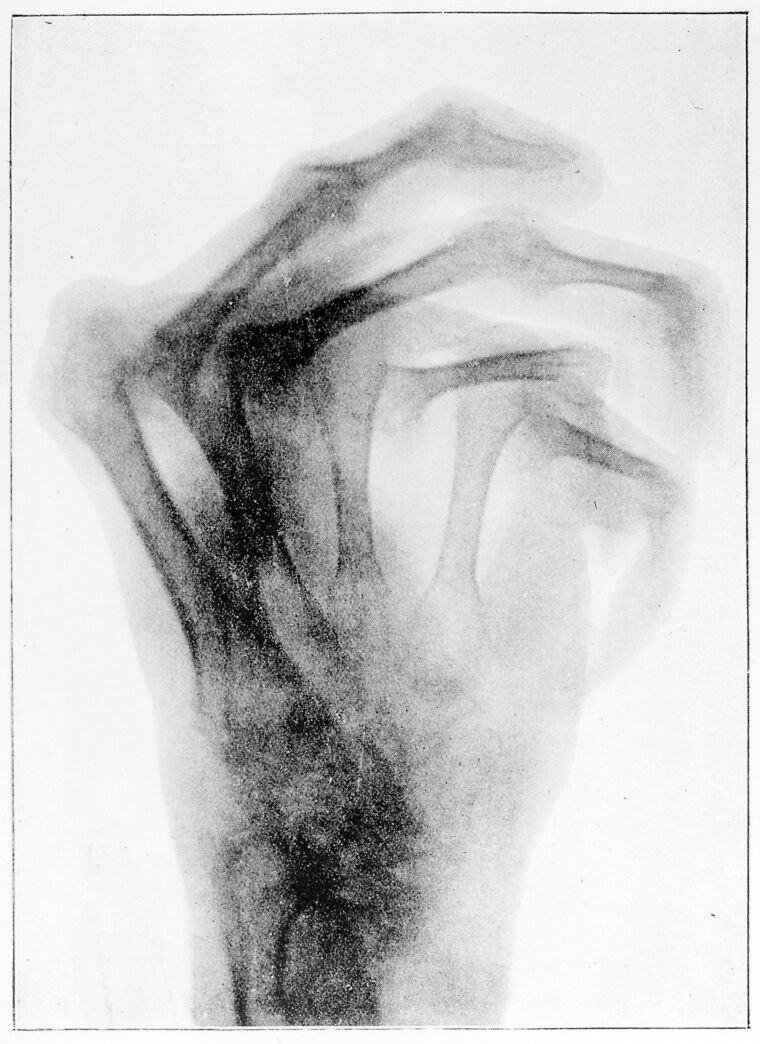

M0019124: X-ray of a hand deformed by osteo-arthritis, c.1897

view M0019124: X-ray of a hand deformed by osteo-arthritis, c.1897

M0019124: X-ray of a hand deformed by osteo-arthritis, c.1897. In copyright. Source: Wellcome Collection.

Reproduction of an x-ray made in c.1897 of a hand deformed by rheumatoid, or osteo, arthritis. Published in Walsh, David: The Roentgen rays in medical work, London : Bailliere, Tindall & Cox, 1907

1 photograph glass plate negative; 8.3 x 10.8 cm